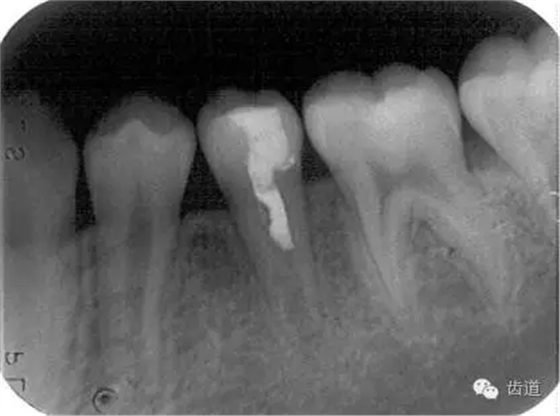

Apexification

Apexogenesis

術(shù)后三個(gè)月

術(shù)后六個(gè)月

術(shù)后兩年

牙根發(fā)育完成根尖閉鎖后, 應(yīng)及時(shí)改做根管充填術(shù)。由于此種牙齒根管粗大而壁薄,宜選用側(cè)壓充填法lateral condensation method或Ultrafil 3D三維注射式熱牙膠根管充填系統(tǒng)。